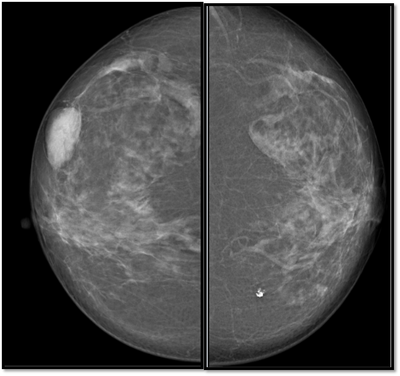

38 year old lady with right breast lump of one year duration.

What is the diagnosis based on mammography and tomosynthesis?